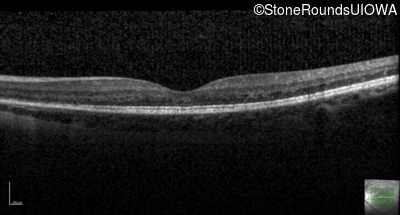

Optical Coherence Tomography - Right - 20/40 +1

Exemplar / OCT Stack